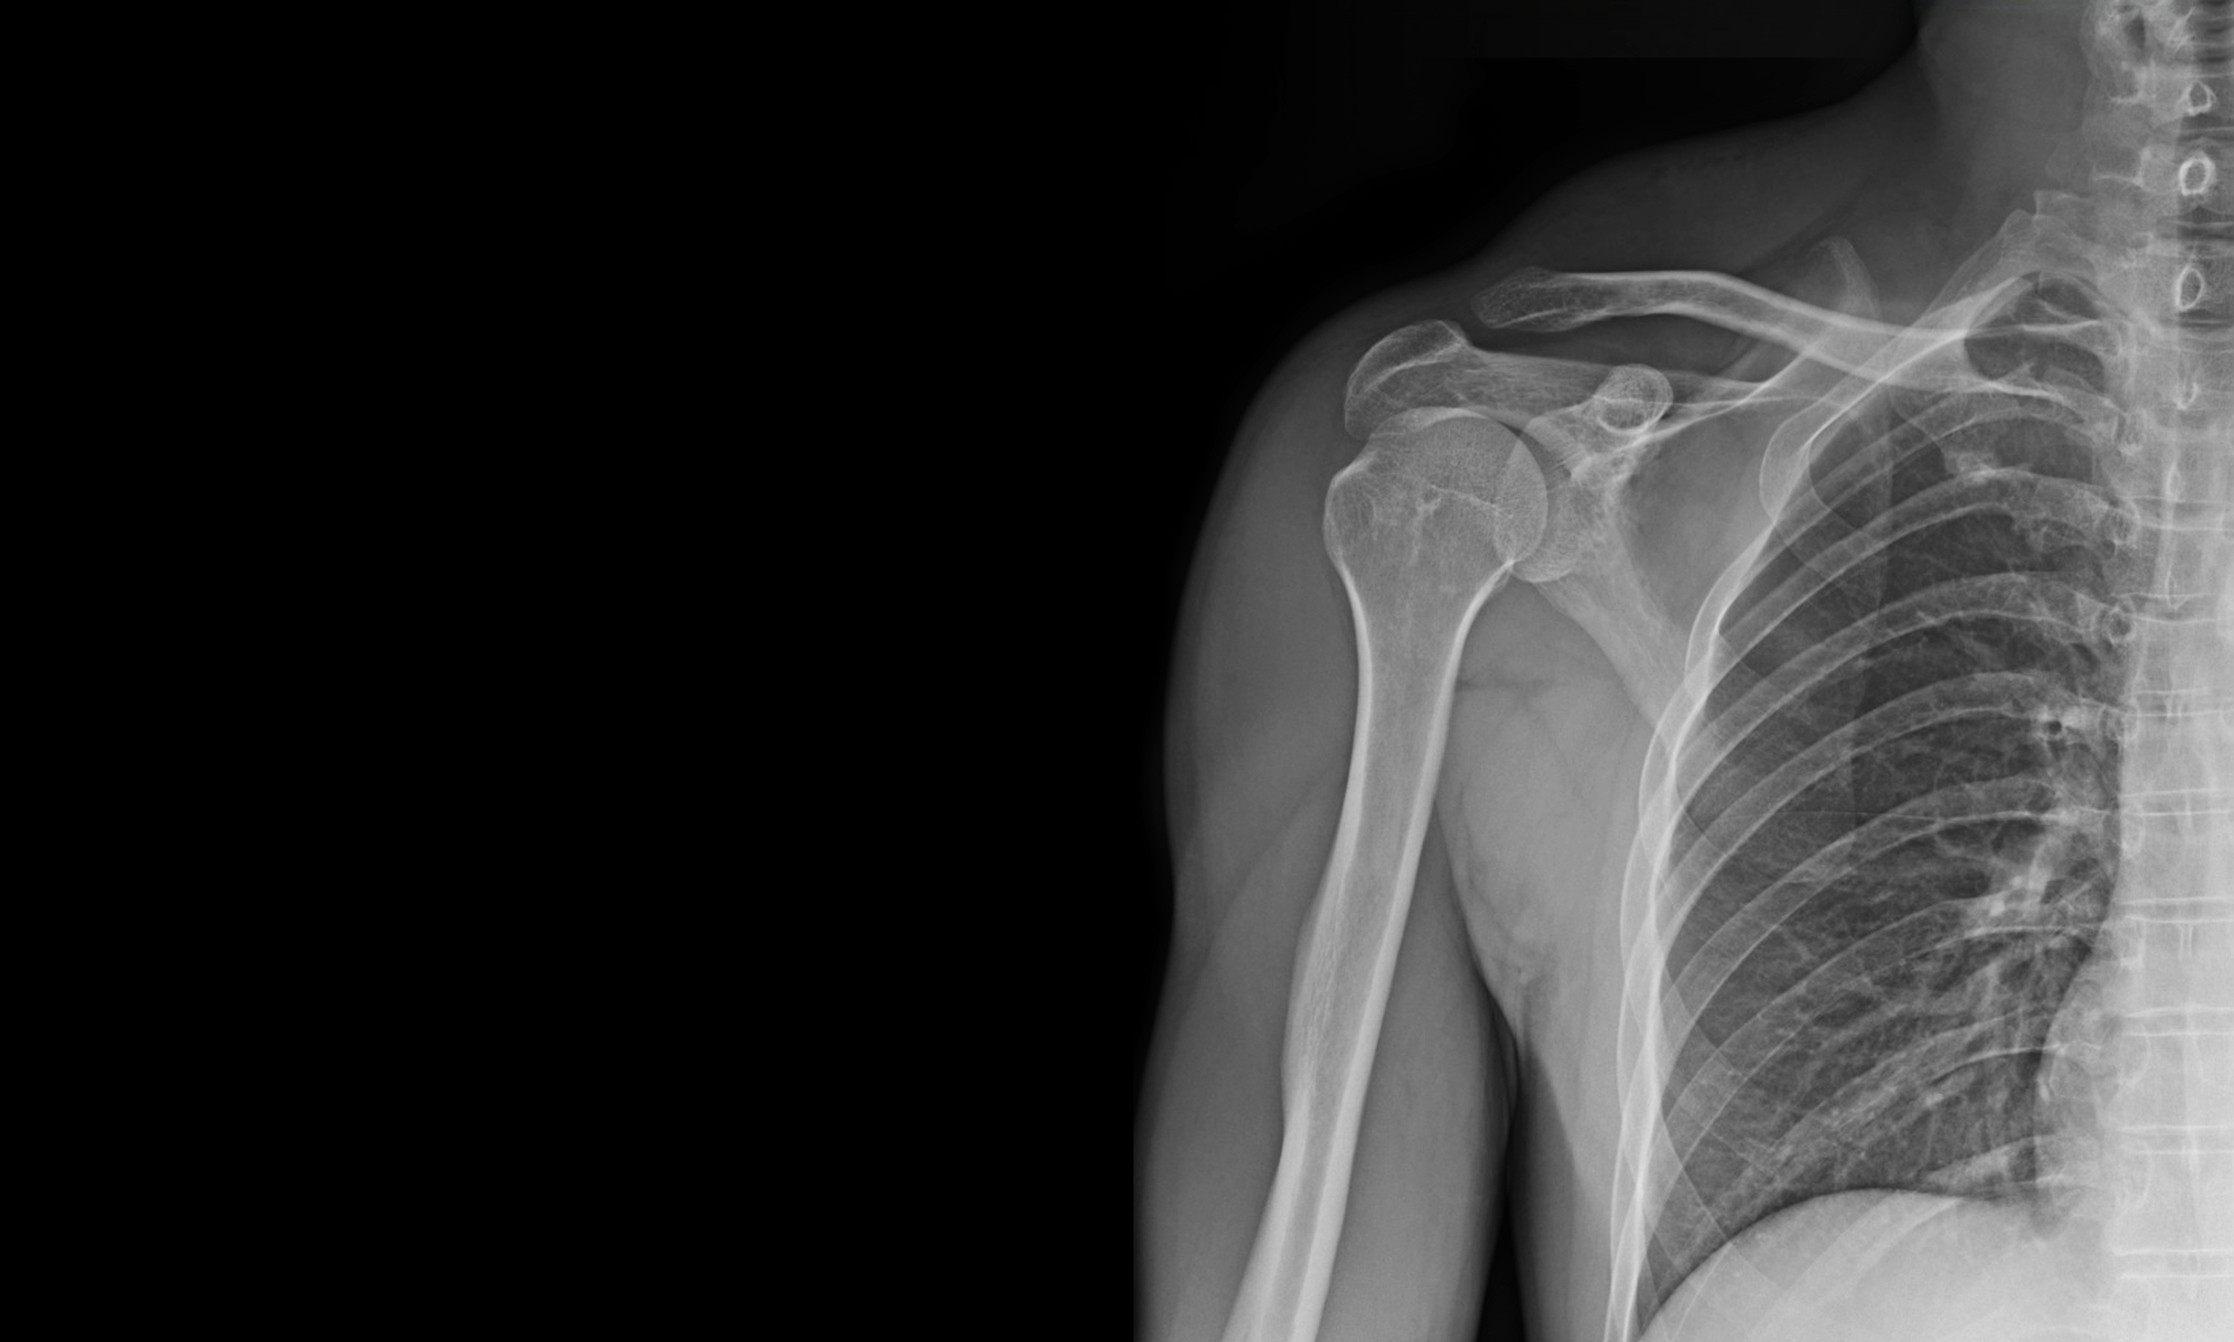

【膊頭甩骹】有些事情不能習慣!肩膊脫臼後不是「啪」回去便算!不治理好易重覆脫臼

的確,膊頭脫臼的初期治療是要把膊頭關節復位。但是之後的跟進和治療卻是更加重要。原因是,肩膊關節在為我們人體中最靈活的關節之一,它的結構比較複雜,除了肩胛骨的臼窩和手臂骨(肱骨)的頭形成肩膊的關節外,還有其他重要的軟組織(如環繞臼窩的盂唇,肩膊關節韌帶及肌肉)去提供膊頭的穩定性,輔助我們日常的上肢功能。當膊頭初次因為撞擊而脫臼的時候,這些重要的軟組織往往會受傷,造成穩定性的缺失。特別是盂唇組織的受傷,像是為肱骨頭開了一道活門,使它容易脫出窩臼。